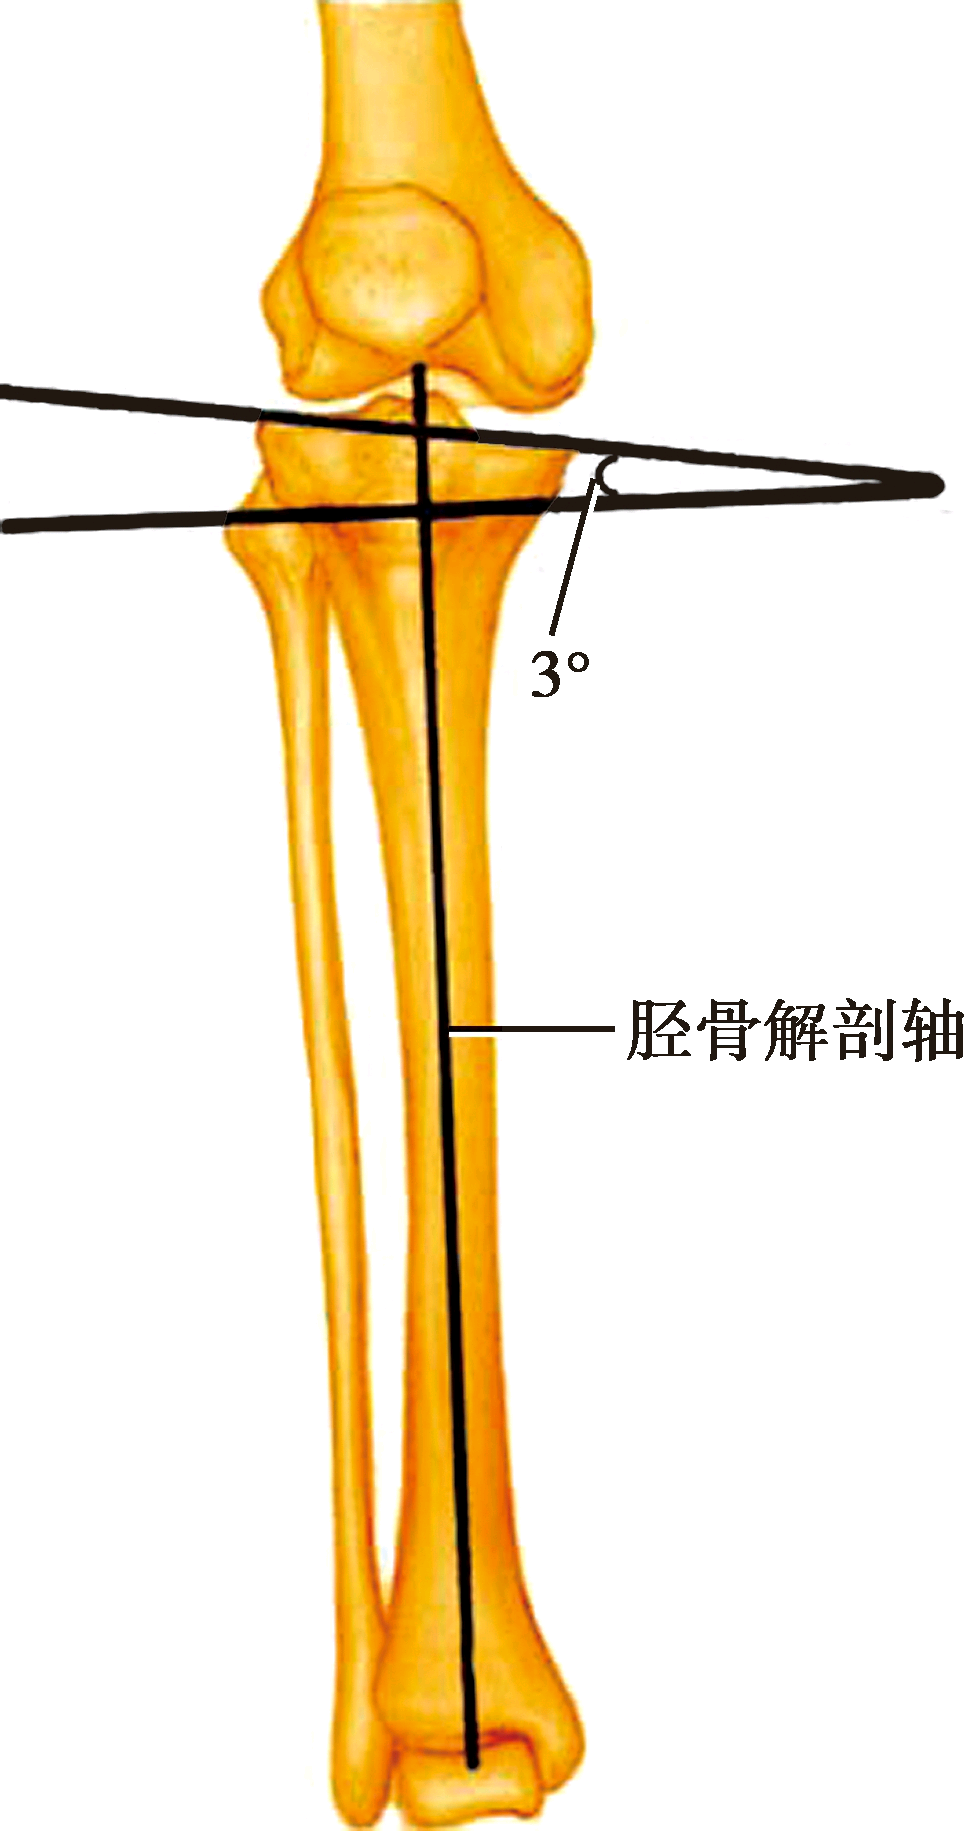

6.胫骨解剖轴及胫骨平台内倾角

胫骨平台内翻3°,截骨平面与机械轴垂直

股骨远端截骨线相对解剖轴外翻6°,方可获得矩形伸直间隙

胫骨解剖轴是胫骨平台关节面的中心与距骨踝关节面中心的连线。胫骨平台内倾角是冠状面上胫骨平台的关节面与胫骨解剖轴的垂直线的夹角,平均约3°。